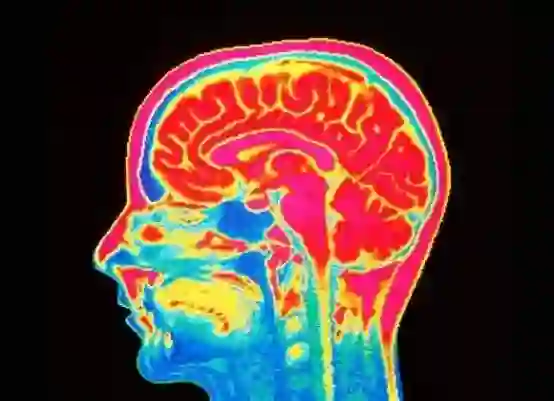

这正是科学家们在大脑扫描和人工智能的帮助下试图做的事情。在近日发表在《自然人类行为》(Nature Human Behavior)上的一项研究中,卡内基梅隆大学和匹兹堡大学的研究人员通过观察自杀个体的大脑在功能磁共振成像机中发光的模式,分析了他们对生与死的想法和感受的不同。然后,他们训练了一种机器学习算法将这些信号分离出来——例如,在提到“死亡”一词时,大脑额叶会变成一个发光的斑点。计算分类器有超过90%准确率,能够识别出有自杀倾向者。此外,它还能从那些有自杀想法的人中,区分出那些真正尝试过自杀的人。

在这一研究中,研究人员对17名年龄在18到30岁之间的年轻人进行了研究,这些人最近向他们的治疗师报告了自己的自杀倾向。然后,他们招募了17名神经正常的参与者作为控制组,并将他们分别放入功能磁共振成像扫描仪中。在这个过程中,受试者会随机看到30个单词。总体来说,10个是正面的,10个是负面的,10个是与死亡和自杀相关的。然后,研究人员让被试者思考出现在他们面前屏幕上的每一个单词。比如说,“‘麻烦’对你意味着什么?”“‘无忧无虑’呢?它的关键概念是什么?”研究人员对每个单词进行了记录,并记录下了受试者的脑血流量,以找出他们大脑的哪些部分似乎在工作。

功能磁共振成像扫描了两组人对“死亡”一词的思考。左边的是有自杀倾向的人。右边是控制组。

然后,他们将这些脑部扫描结果输入机器学习分类器。对于每个单词,他们都会告诉这个算法,扫描结果是属于有自杀倾向者,还是属于控制组,他们对所有30个单词的结果进行了测试。最后,分类器可以可靠地分辨扫描结果,并在判断那个人是否曾考虑过自杀方面有91%的成功率。为了观察它是否能更广泛地分析人们,研究人员又把21名有自杀倾向者的扫描结果交给了它,因为他们的脑部扫描结果太乱,他们被排除在主要分析之外。在分析“死亡、残忍、麻烦、无忧无虑、善良和赞扬”这六个最具歧视的概念后,分类器发现那些想到过自杀的人的准确率为87%。